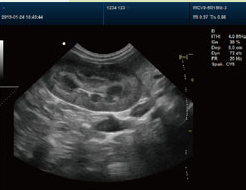

彩超穿刺是一种在超声实时引导下,用穿刺针精准进入体内病灶并取样或治疗的操作,主要用于组织活检、积液引流或药物注射。其核心步骤包括定位病灶、消毒麻醉、实时穿刺、取样处理,具有精准安全、创伤小的特点。 一、操作前准备 1、患者评估:医生会先通过超声确认病灶位置、大小及周围血管分布,评估穿刺可行性。患者需告知过敏史、用药情况(如抗凝血药需提前停药)。 2、签署知情同意书:医生会说明操作目的、风险及注意事项,患者需签字确认。 3、体位调整:根据病灶位置,患者需采取仰卧、侧卧等姿势,并保持稳定不动。 二、操作过程 1、定位与标记: 超声探头涂抹耦合剂后,在皮肤表面滑动扫描,找到最佳穿刺路径,避开重要血管和器官,用记号笔标记进针点。 2、消毒与麻醉: 对穿刺区域消毒并铺无菌巾,用细针在皮肤及皮下注射局部麻醉药,减轻疼痛。 3、实时引导穿刺: 医生持穿刺针沿预定角度缓慢进针,超声屏幕实时显示针尖位置。到达病灶后,通过负压吸引(如活检枪)抽取组织或液体。 4、样本处理: 取出样本放入保存液或玻片,送病理检查;若为引流,则连接引流袋排出积液。 三、术后处理 1、止血与包扎:穿刺点按压5-10分钟止血,覆盖无菌敷料,必要时用绷带加压。 2、观察与休息:患者需在留观区休息30-60分钟,监测有无出血、疼痛加剧或头晕等异常。 3、注意事项:24小时内避免剧烈运动,保持穿刺部位干燥;若出现肿胀、发热需及时就医。 四、技术优势与风险 优势:超声引导可实时观察穿刺路径,减少误伤风险;创口仅针眼大小,恢复快。 风险:少数可能出现局部出血、感染或气胸(如胸部穿刺),但发生率不足1%,及时处理即可控制。 五、适用场景 1、诊断用途:疑似肿瘤、甲状腺结节、乳腺肿块等需病理确诊。 2、治疗用途:肝脓肿引流、关节腔注射药物或卵巢囊肿抽吸。 彩超穿刺的准确性高度依赖医生经验及设备清晰度,建议选择正规医疗机构操作。